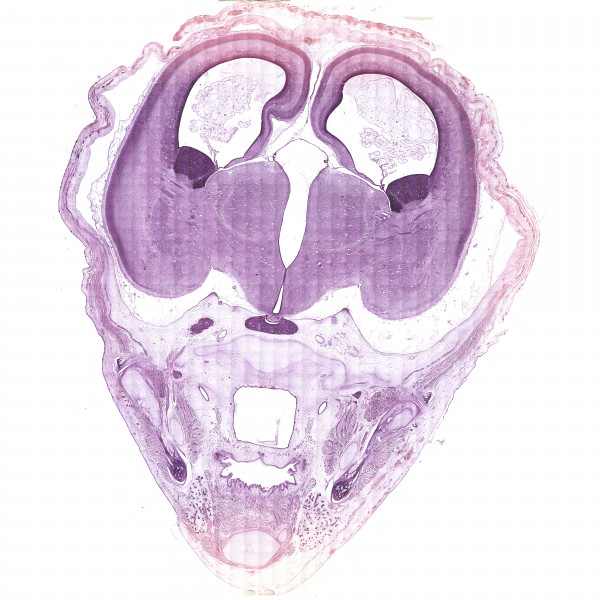

Fig.1 Main fissure of the brain medial surface at 11 weeks of gestational development

The period of cortpcal plate formation continued during the 11th PCW. In the areas of neocortical formation, the ventricular zone (VZ), subventricular zone (SVZ), intermediate zone (IZ), corical plate (CP), and marginal zone (MZ) were revealed both in the lateral and medial walls of the hemispheres. The cortical plate thickness was significantly larger than that of ventricular zone. Compared with the fetuses at Carnegie stage 21, the thickness of the walls was increased by 1.5-2 fold.

The dorsomedial wall of the hemisphere was much narrower than the lateral one, while the thicknesses of the ventricular zone in the medial and lateral walls did not significantly differ.